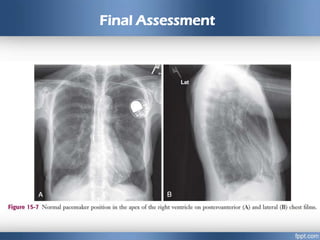

Final Assessment

• Assess pacemaker function again, and take a chest film to ensure

proper positioning. Ideal positioning of the pacing catheter is at the

apex of the right ventricle

• A 12-lead ECG tracing should be obtained after placement of the

transvenous pacemaker. If the catheter is within the right ventricle, a

left bundle branch pattern with left axis deviation should be evident in

paced beats

• If an RBBB pattern is noted, coronary sinus placement or left

ventricular pacing secondary to septal penetration should be

suspected.